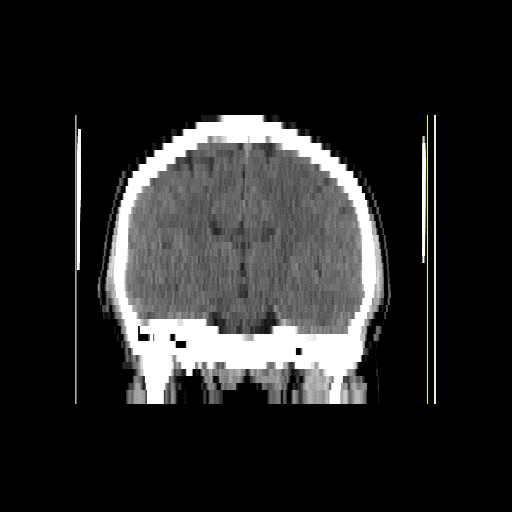

Final project for CS3102 - Advanced Data Structures at University of Engineering and Technology (UTEC).The final project for CS3102 - Advanced Data Structures consisted of implementing an octree data structure for 3D compression. To test the correct functionality of the algorithm, a set of MRI images were used as benchmark. The idea is to visualy compare images obtained from the non-compressed volume vs. those from the 3D image stored at the octree. The project was developed in C++ and all source code can be found here. The following article presents some of the images and videos obtained from the renderer processing a set of MRI images as a volume.

Frontal